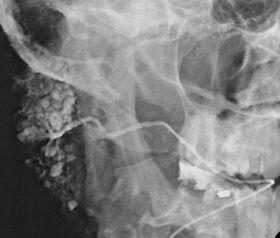

Sialographie Verdacht auf Sjoegren-Syndrom.jpg

Sialogram in a patient suspected of Sjögren's syndrome

Sialography (also termed radiosialography) is the radiographic examination of the salivary glands. It usually involves the injection of a small amount of contrast medium into the salivary duct of a single gland, followed by routine X-ray projections.[1]

The resulting image is called a sialogram.

This study is interpreted by evaluating the morphology of the salivary ducts for obstructions and chronic inflammation. Sialodochitis is a term describing dilation of the ducts caused by repeated inflammatory or infective processes. There is also irregular salivary duct stricture (narrowing) of the duct, which creates an appearance known as "sausage link" pattern on a sialogram. Suggestions of abscesses and autoimmune diseases such as Sjögren syndrome can also be elicited. Sialadenitis is inflammation of the salivary glands, which may cause acinar atrophy and create an appearance known as "pruning of the tree" on a sialogram, where there are less branches visible from the duct system. A space occupying lesion that occurs within or adjacent to a salivary gland can displace the normal anatomy of the gland. This may create an appearance known as "ball in hand" on an sialogram, where the ducts are curved around the mass of the lesion.[5]